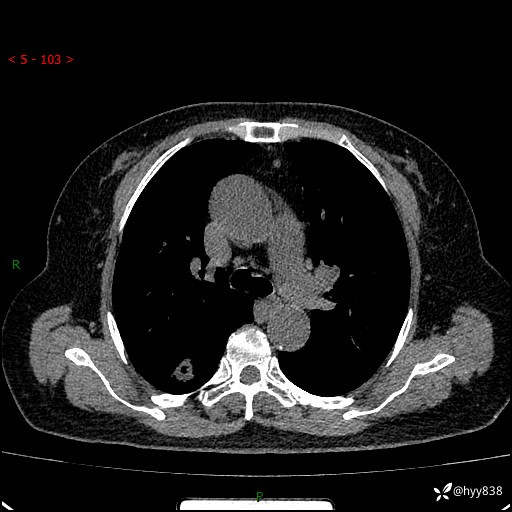

71岁/女,发现肺结节1月。偶然发现孤立肺结节,邻近叶间裂凹陷---结果公布(再回首)

【患者信息】:71岁/女

【主诉】:发现肺结节1月

【现病史及既往史】:2024年9月患者因“胆囊结石”于我院肝胆外科住院,期间完善胸部CT提示:右下肺结节灶,高危结节?感染?,病程中无畏寒发热,无咳嗽、咳痰,无活动后气短,无心慌胸闷,无胸痛、咯血,无头晕头痛,无腹痛腹泻,无四肢肌肉酸痛等不适,当时建议其择期复查。今日患者为求进一步复查就诊于我院,完善胸部CT提示:右肺结节,较前一致,遂门诊“肺部结节”收入我科。 自本次起病以来,患者精神、饮食、睡眠可,大小便正常,体力、体重未见明显异常。

【检查】:胸部CT平扫+增强